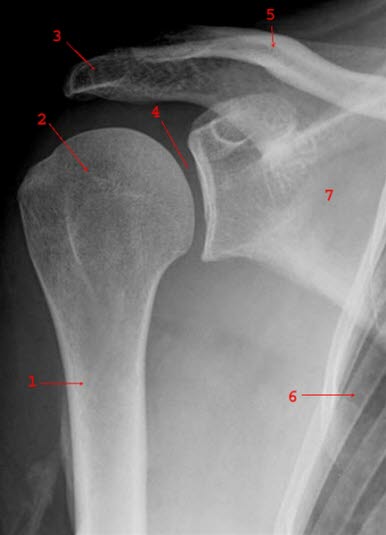

SkulderleddetLuksasjon av skulderleddet betyr at skulderen er "ute av ledd". Skulderleddet dannes i møtepunktet mellom skulderbladet (scapula) og overarmsbeinet (humerus). Skulderbladet er leddskålen, og den beskytter godt mot forskyvninger av leddhodet oppover og bakover. Fremover derimot er det først og fremst muskler som hindrer at leddhodet forskyves, og det kan ved kraftige skader bli en for svak beskyttelse.

Røntgenbilde av normalt skulderleddDiagnosen er vanligvis lett å stille. Plutselig oppstått smerte og tap av bevegelighet etter en skade er den typiske sykehistorien. Ved skulderundersøkelsen vil det ved fremre luksasjon være et søkk i skulderbuen (den normale skulderkonturen er endret), og hodet til overarmsbeinet kan kjennes fortil i armhulen. Om mulig vil man forsøke å få skulderen på plass igjen, reponert, så snart som mulig. Etter reponering, ved mislykket reponering eller ikke utført reponering, bør vedkommende undersøkes av lege. Legen vil kontrollere nerver og blodkar i armen for å utelukke skade av disse strukturene. Røntgen av skulderen er nødvendig. I sykehus tas det ofte røntgenbilder før og etter behandling.